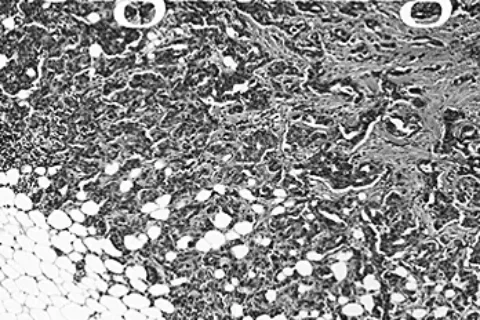

《科学·信号》2020.10.20   肿瘤干细胞(CSCs)是驱动肿瘤进展、适应应激及抵抗化疗的关键细胞亚群,其干细胞样特性为癌症治疗带来了严峻挑战。湖南元初生物关注到,近期一项研究揭示了阿司匹林在靶向肿瘤干细胞方面的新机制,这为提升基底样乳腺癌的化疗疗效提供了潜在策略。   研究表明,在侵袭性乳腺肿瘤模型及肿瘤干细胞培养体系中,阿司匹林能够通过缓解多能性因子对转录辅助因子SMAR1的抑制作用,进而显著抑制药物外排泵ABCG2的合成。这一作用机制使得阿司匹林能够有效阻止阿霉素所诱导的SMAR1…